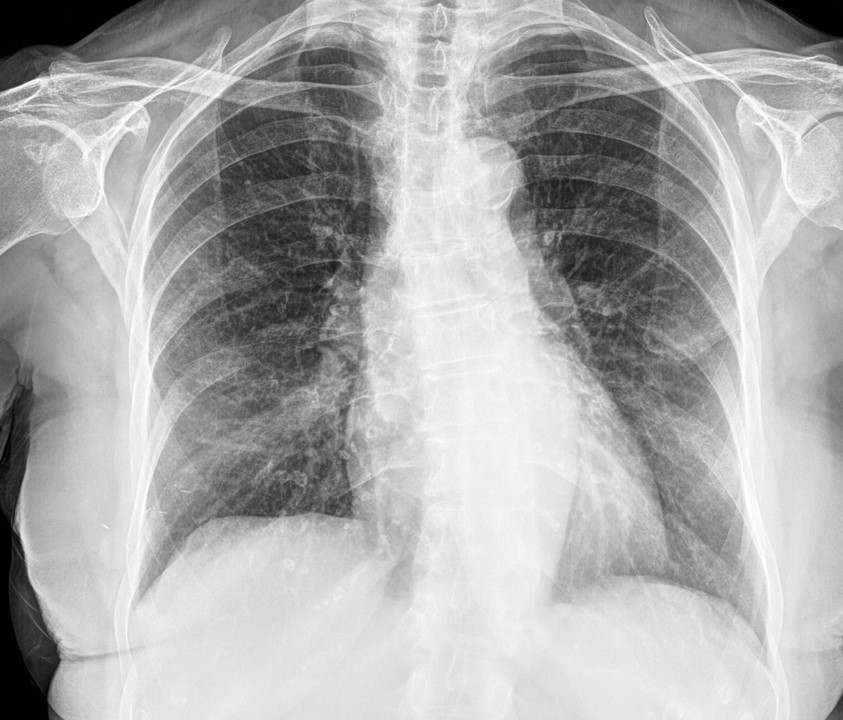

In this project, we will develop a way to use chest radiographs (CXR) for COVID19 infection detection. This could be a fast way to early determine COVID19 infection and could be another stone in the effort to block the virus.

Five times more deadly than the flu, COVID-19 causes significant morbidity and mortality. Like other pneumonias, pulmonary infection with COVID-19 results in inflammation and fluid in the lungs. COVID-19 looks very similar to other viral and bacterial pneumonias on chest radiographs, which makes it difficult to diagnose. Your computer vision model to detect and localize COVID-19 would help doctors provide a quick and confident diagnosis. As a result, patients could get the right treatment before the most severe effects of the virus take hold.

Currently, COVID-19 can be diagnosed via polymerase chain reaction to detect genetic material from the virus or chest radiograph. However, it can take a few hours and sometimes days before the molecular test results are back. By contrast, chest radiographs can be obtained in minutes. While guidelines exist to help radiologists differentiate COVID-19 from other types of infection, their assessments vary. In addition, non-radiologists could be supported with better localization of the disease, such as with a visual bounding box.

In this competition, you’ll identify and localize COVID-19 abnormalities on chest radiographs. In particular, you'll categorize the radiographs as negative for pneumonia or typical, indeterminate, or atypical for COVID-19. You and your model will work with imaging data and annotations from a group of radiologists.